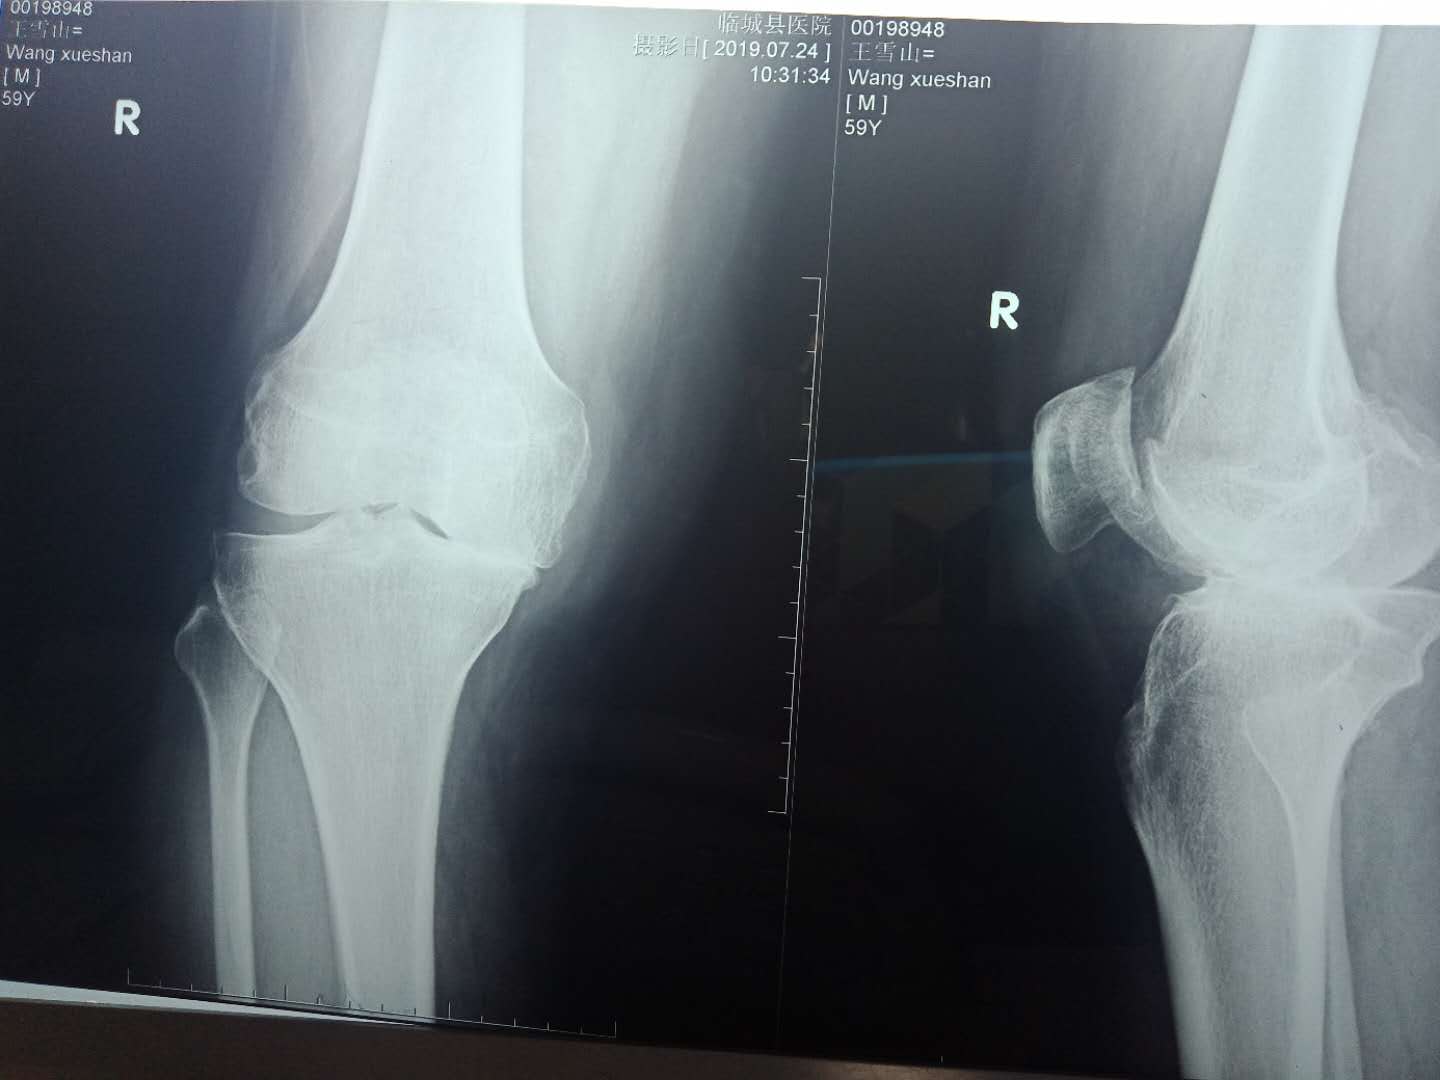

x线平片未见异常,会有关节间隙狭窄,提示关节软骨开始变薄。起初,无负载时,关节间隙正常,轴承后关节间隙狭窄。病程晚期,关节间隙明显狭窄,软骨下可出现微裂缝,骨质硬化,关节边缘尖锐,形成骨赘。骨关节炎的典型症状可能是在负重处的软骨下出现骨囊。通过 CT、MRI检查可明确病变部位。